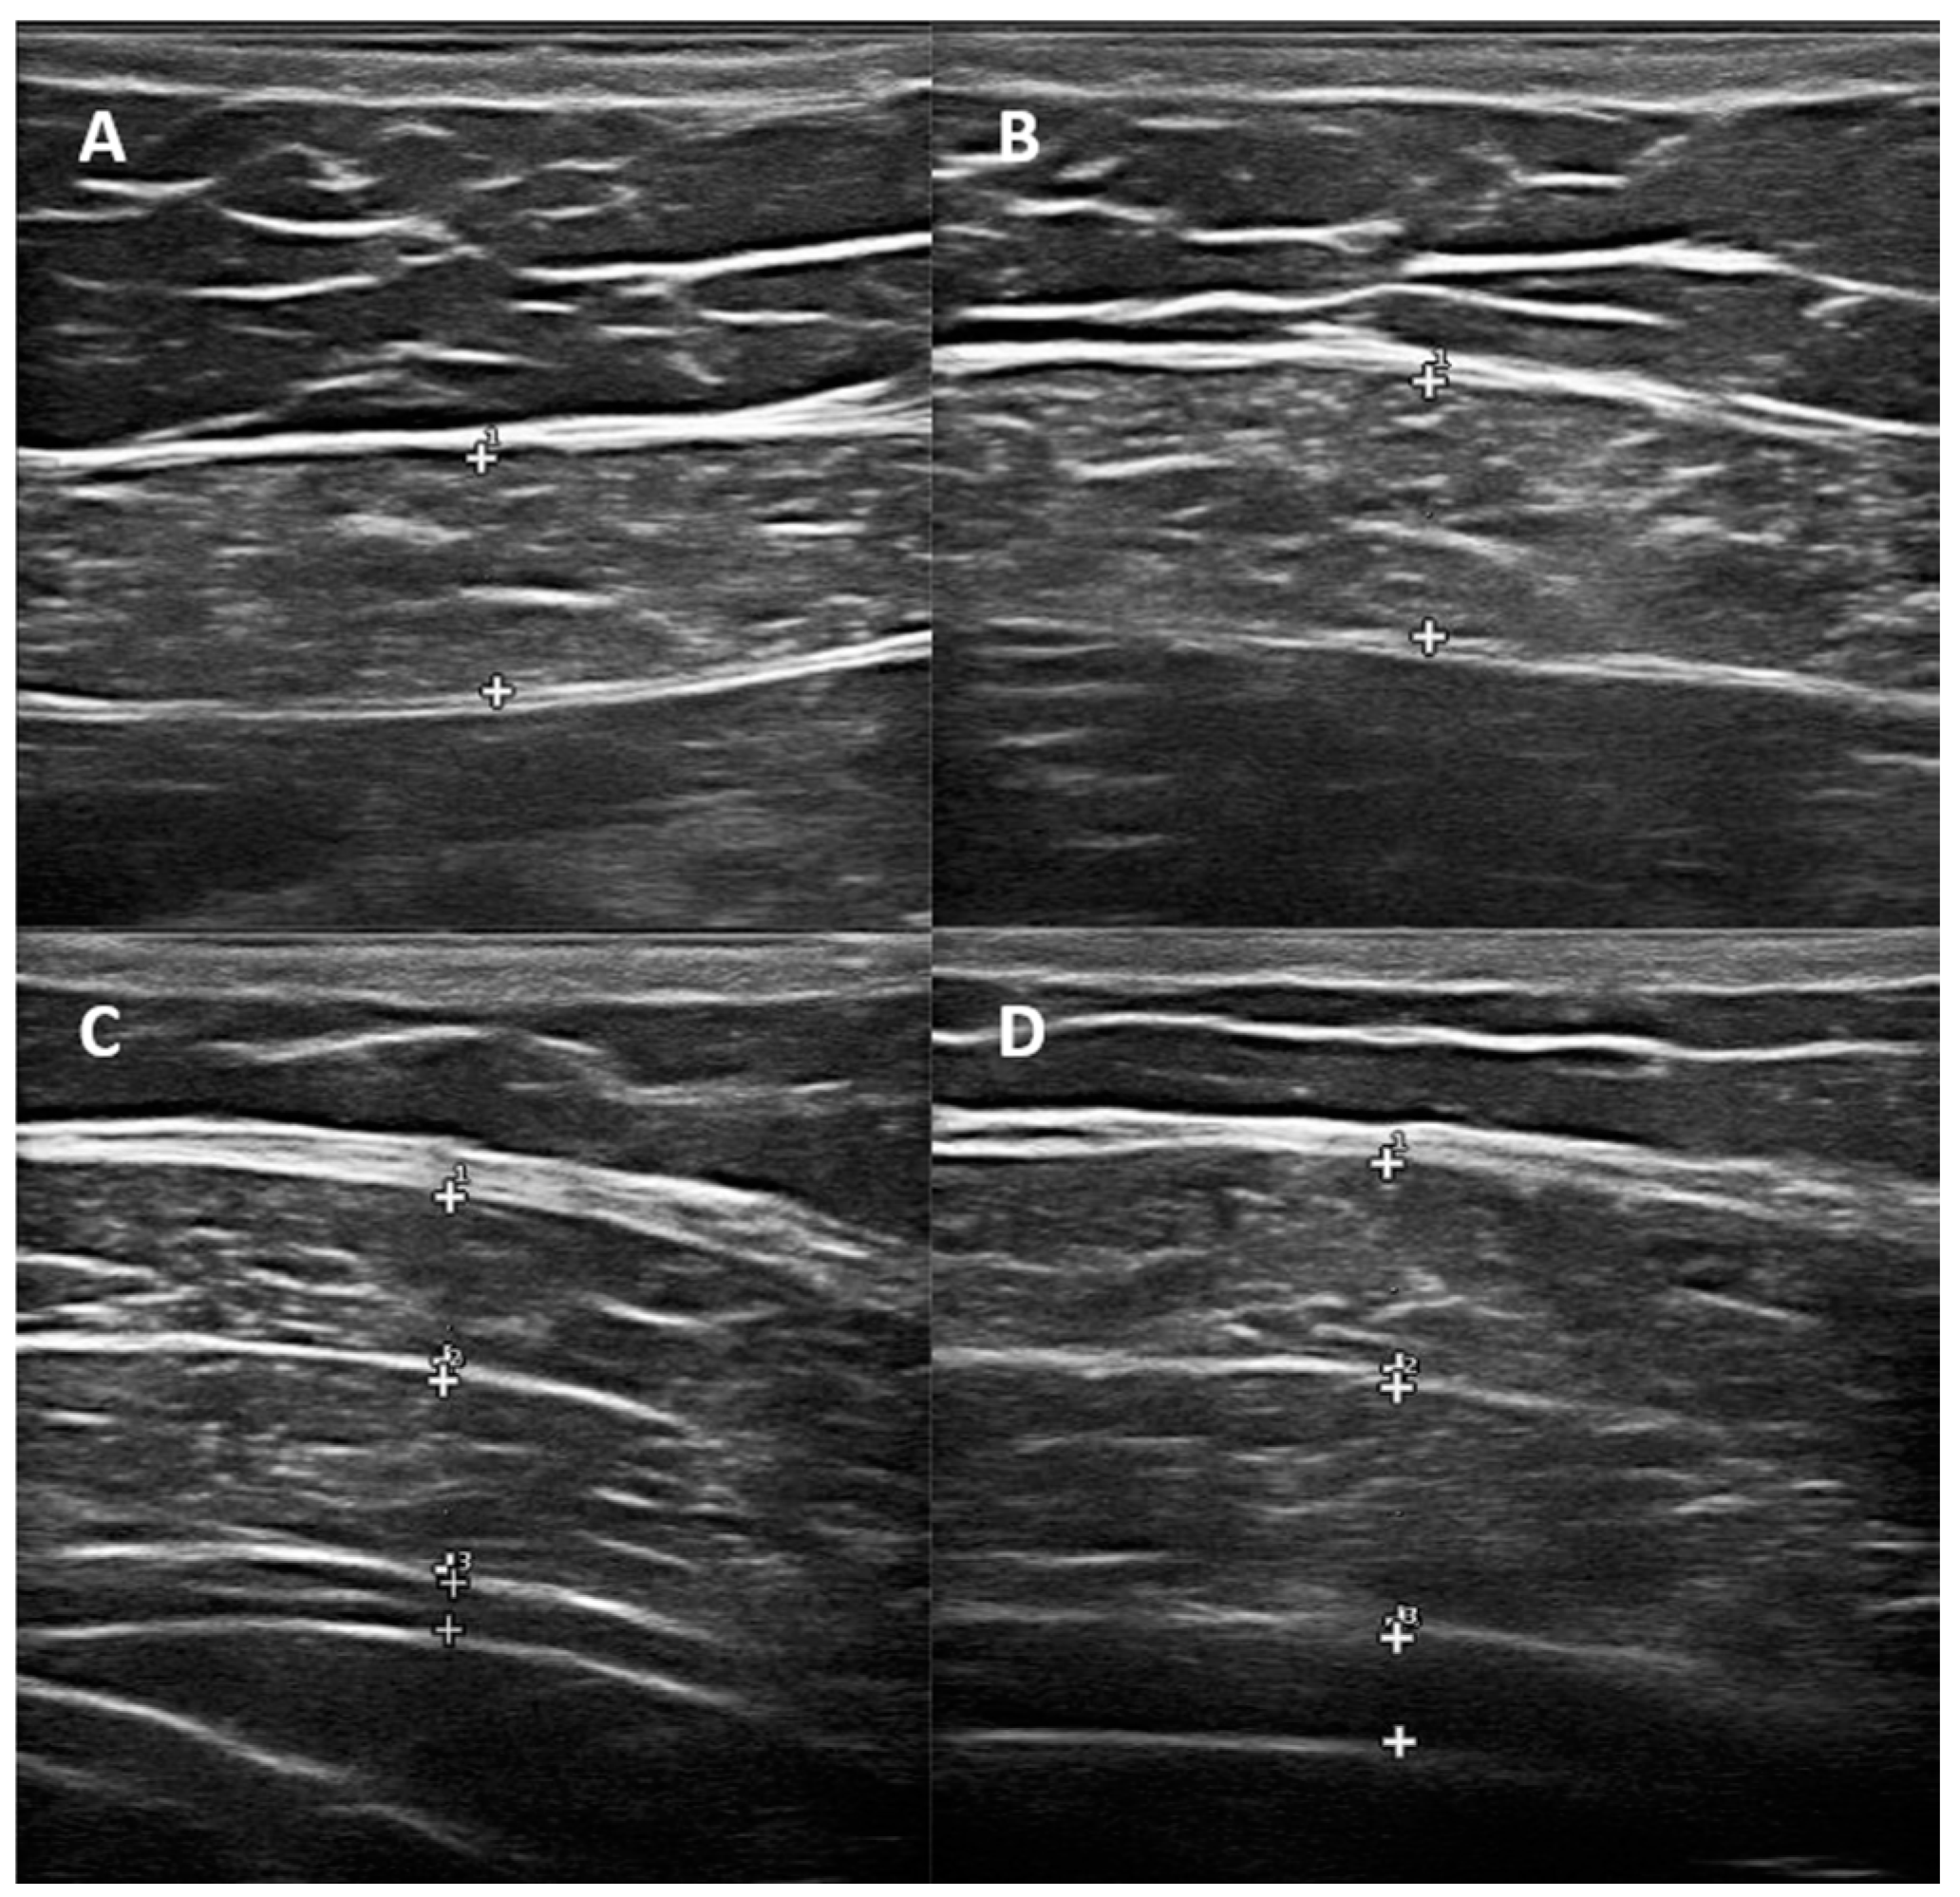

2.2. Ultrasonographic Evaluation